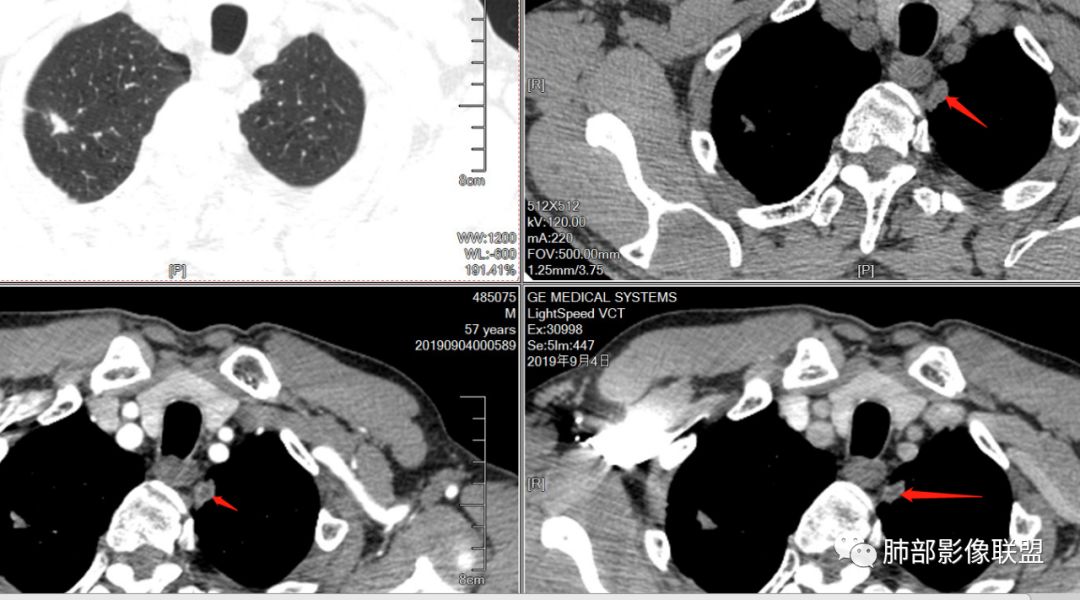

男,57岁,因“体检发现右上肺占位”入院。凝血常规、血常规、肾功能等均未见明显异常。

CT值:

平扫  18                          动脉期  28                      静脉期 41

双肺尖斑片状影及结节影,边缘平直为主,边缘可见胸膜牵拉,考虑结核,鉴别诊断腺癌,本病特点,多灶性,多态性,胸膜牵拉线纤细。

右上肺病灶,边缘平直,有卫星灶,强化不明显,考虑结核可能大

结核。右上肺结节密度均匀轻度强化,结节边缘清晰有小分叶,周围细长软毛刺,有卫星灶。左上肺近纵隔类似片状结节。

右肺尖结节边缘可见卫星灶,结节边缘平直凹陷、长毛刺,外观上有炎性结节的特点

增强扫描右肺尖结节强化不明确,但左肺尖后段结节出现了典型的环形强化

右肺上叶结节灶,边缘膨隆,有毛刺,胸膜牵拉,轻度强化,左肺上叶结节灶环形强化,左肺考虑结核,右肺结节灶,不排除疤痕癌。

两肺上叶结节影,右肺结节边缘清晰,平直,有胸模牵拉,有卫星灶,强化不明显,左肺结节周边强化,两肺门淋巴结肿大,整体考虑结核。

右肺上叶结节,边缘部分膨隆,毛刺,内部有强化增粗血管影,边缘有空泡,胸膜有牵拉,考虑腺癌。鉴别结核。

右肺尖结节边缘可见分叶,结节边缘有毛刺,但左肺尖后段结节出现了典型的环形强化,考虑炎性病变,右上肺结节鉴别腺癌。还有患者食管上段壁明显增厚。

两上肺(右尖左尖后)都有小结节影,右肺尖结节边缘可见卫星灶,结节边缘平直凹陷、长毛刺,部分膨隆,增强扫描右肺尖结节强化不明确;左肺尖后段结节边缘平直凹陷,增强见环形强化。考虑结核可能性大,右上肺注意鉴别腺癌。